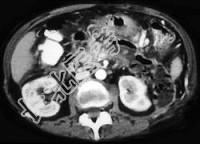

- 单项选择题女性,34岁, 寒战、高热、急性中上腹偏左腹痛,压痛, CT扫描如图,最可能的诊断是 ( )

A、急性胰腺炎

B、胰腺脓肿

C、慢性胰腺炎急性发作

D、胰腺癌

E、胰腺转移癌